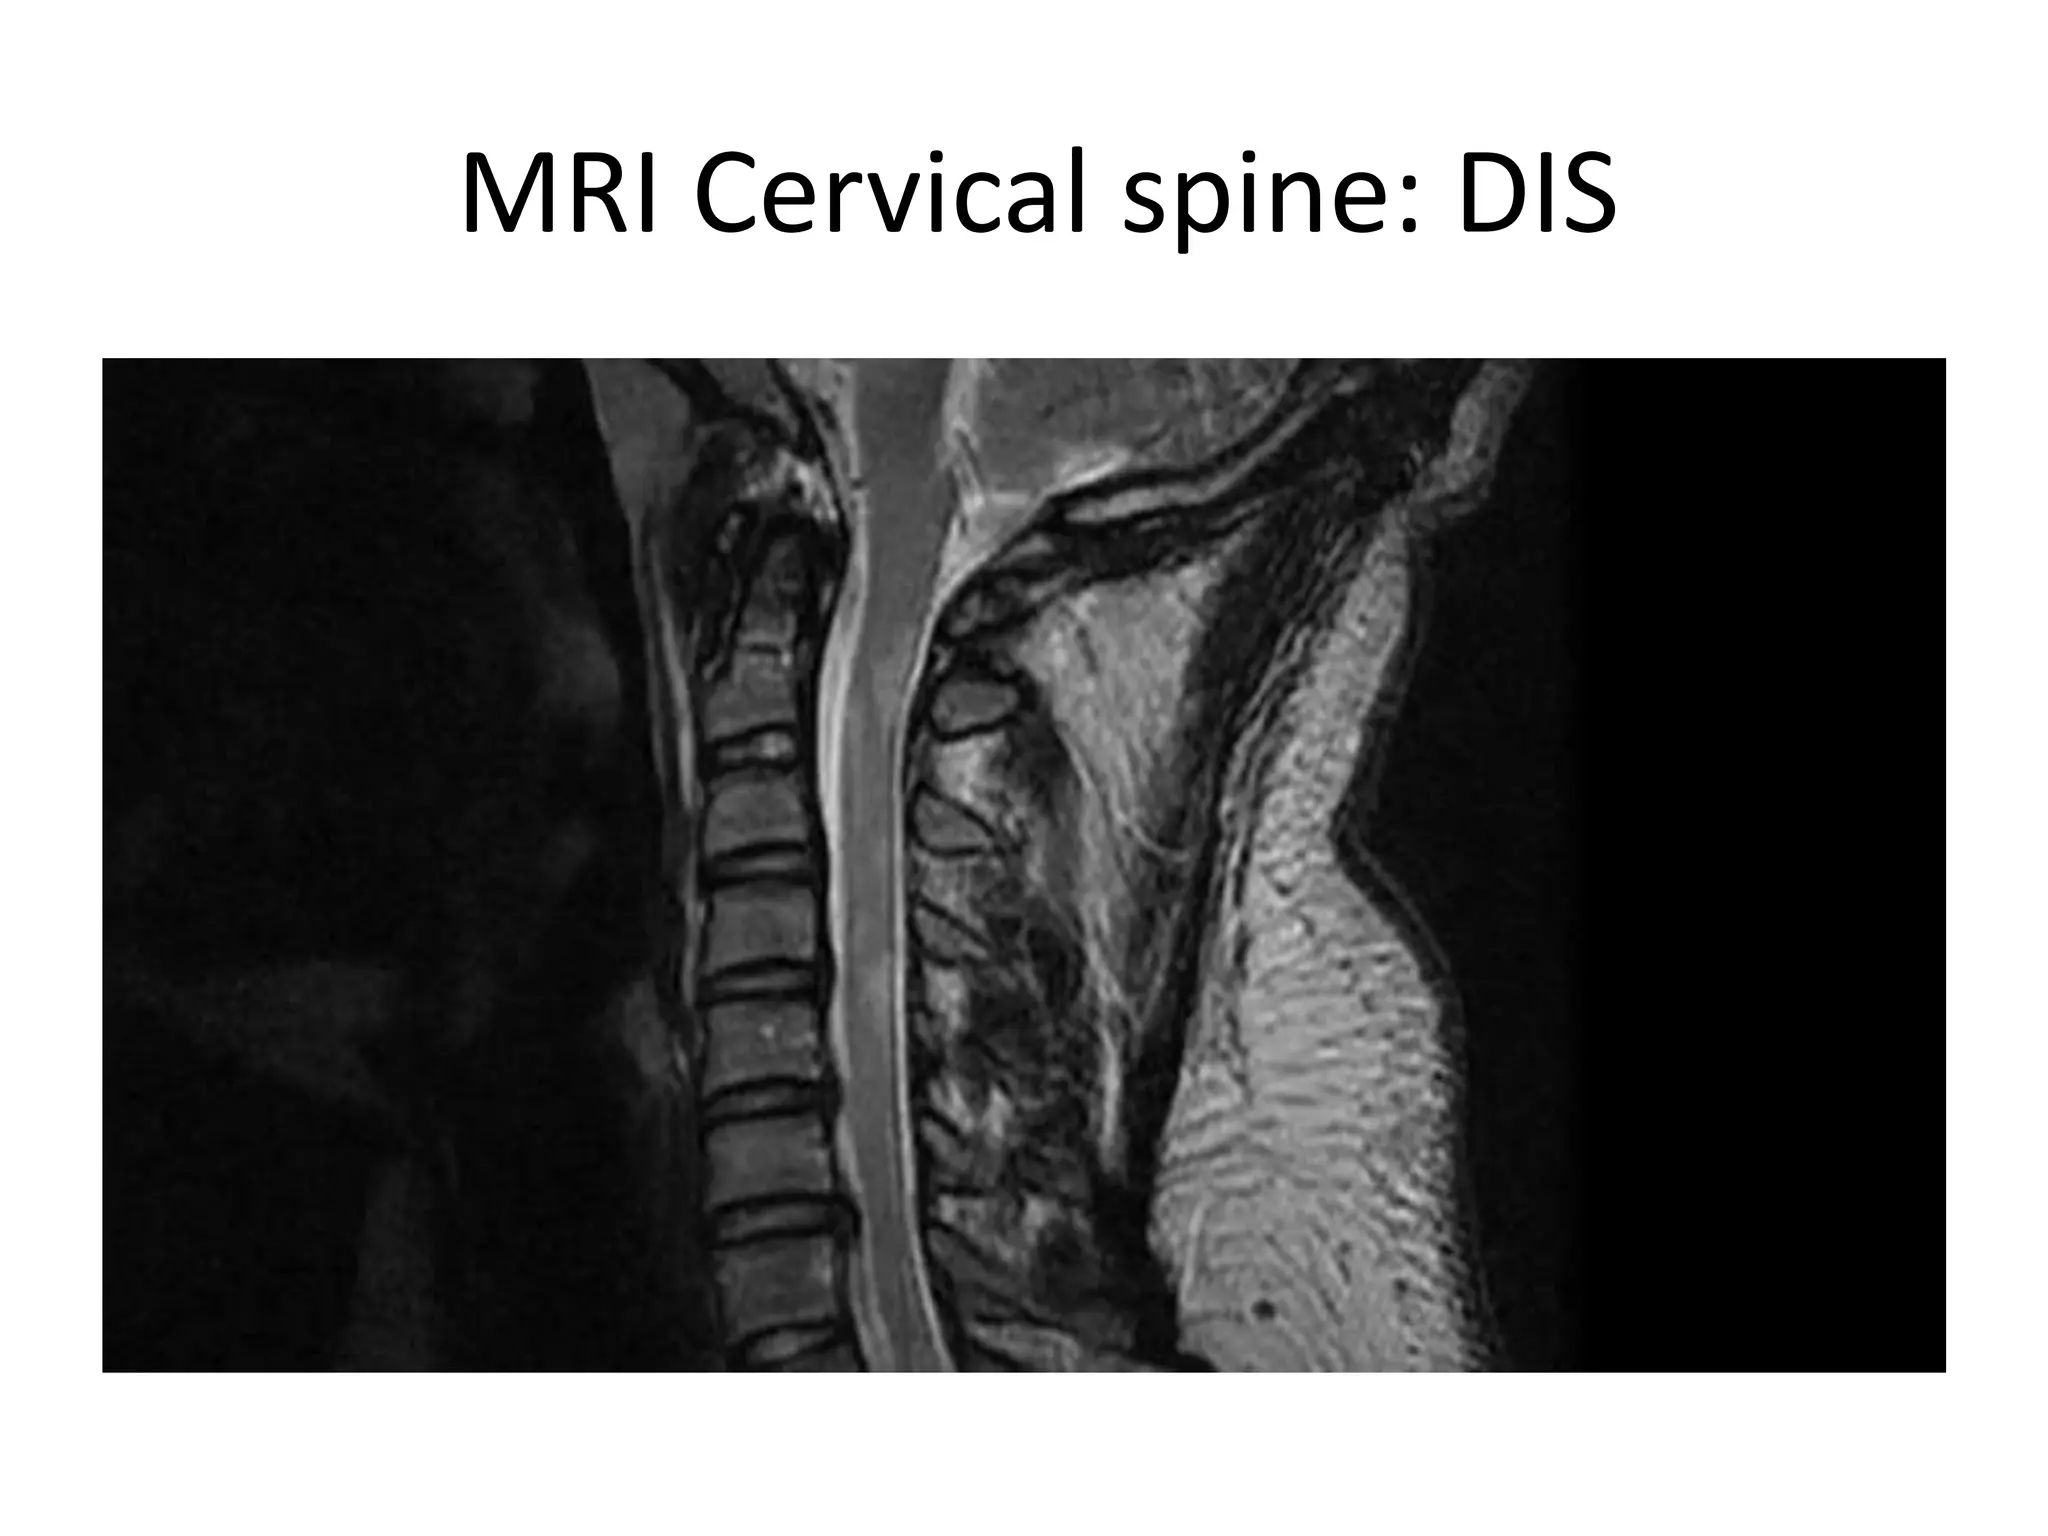

MRI Cervical spine: DIS

Case 1: MRICervical spineTWI

Case 2 • InAugust 2011 he reported dizziness, ataxia and diplopia • He was treated with pulse steroids with marked recovery. • He was clinically stable, and was advised to restart Rebif. • In Jan 2012, EDSS:1, AI:0. • MRI in June 2012 showed new cerebellar lesions, with no enhancement. • In Oct 2012, he came in with a mild relapse and was treated with pulse steroids. • An MRI in Dec 2012 showed worsening lesion load, and he was advised to start Tysabri after JCV serology. • He started Tysabri in Dec 2012, and till 5 months post Tysabri , there were no active lesions.